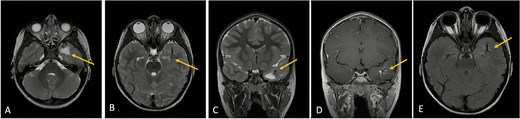

MRI with and without gadolinium contrast identified a vascular lesion consistent with a DVA in the left anterior temporal lobe. This showed typical caput medusae venous morphology. Adjacent white matter T2/FLAIR hyperintensities were present without diffusion restriction or blooming on gradient-echo sequences. No abnormal contrast enhancement was noted, and major venous sinuses were patent (Figs 1 and 2).

Axial lower cut (A)/axial higher cut (B)/coronal (C) T2-weighted MRI of the brain shows a prominent area of T2 hyperintensity (arrow) in the white matter of the left anterior temporal lobe, adjacent to the DVA. The DVA itself is clearly delineated on the contrasted sequence (D) and its draining veins contribute to the local anatomy (arrow). (E) Axial FLAIR (fluid-attenuated inversion recovery) highlights the abnormal hyperintensity in the left anterior temporal lobe white matter (arrow), suppressing the cerebrospinal fluid signal and making the white matter changes more conspicuous. This represents chronic changes such as gliosis or edema.